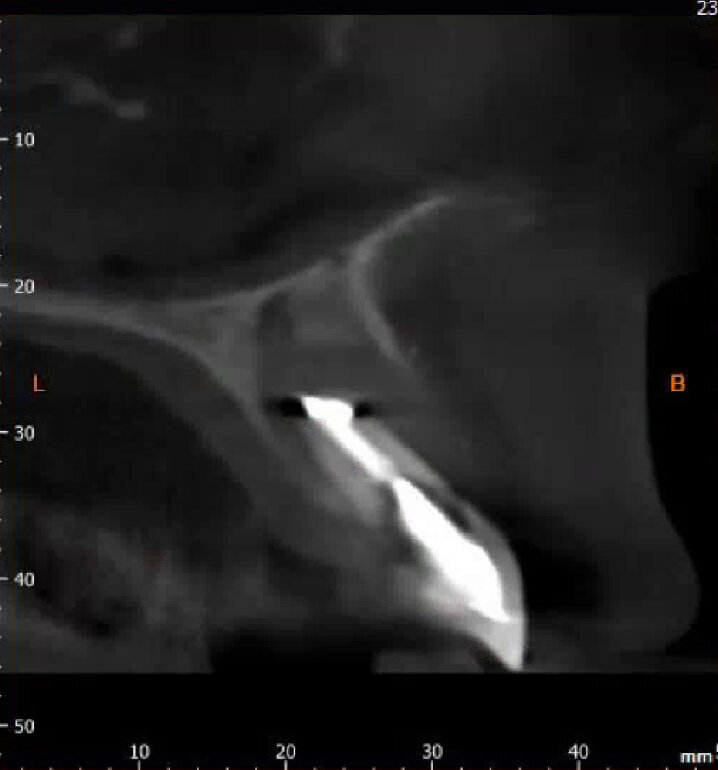

We are routinely used to 2-D radiographic imaging techniques in dentistry, but with the availability and access to CBCT scanning devices now, we are able to assess bone quantity and quality of proposed implant surgical sites. With ever-reducing doses of 3-D imaging and improving accuracy, we are able to use CBCT scans, combined with clever software packages such as coDiagnostiX (Dental Wings), to plan safe and accurate implant placement and restoration. We are able to preoperatively plan precise implant placement with safe surgical margins away from important anatomical structures, such as the inferior alveolar nerve or maxillary sinus. From this, we are then able to design and either mill or print a surgical guide to use for precise implant placement.